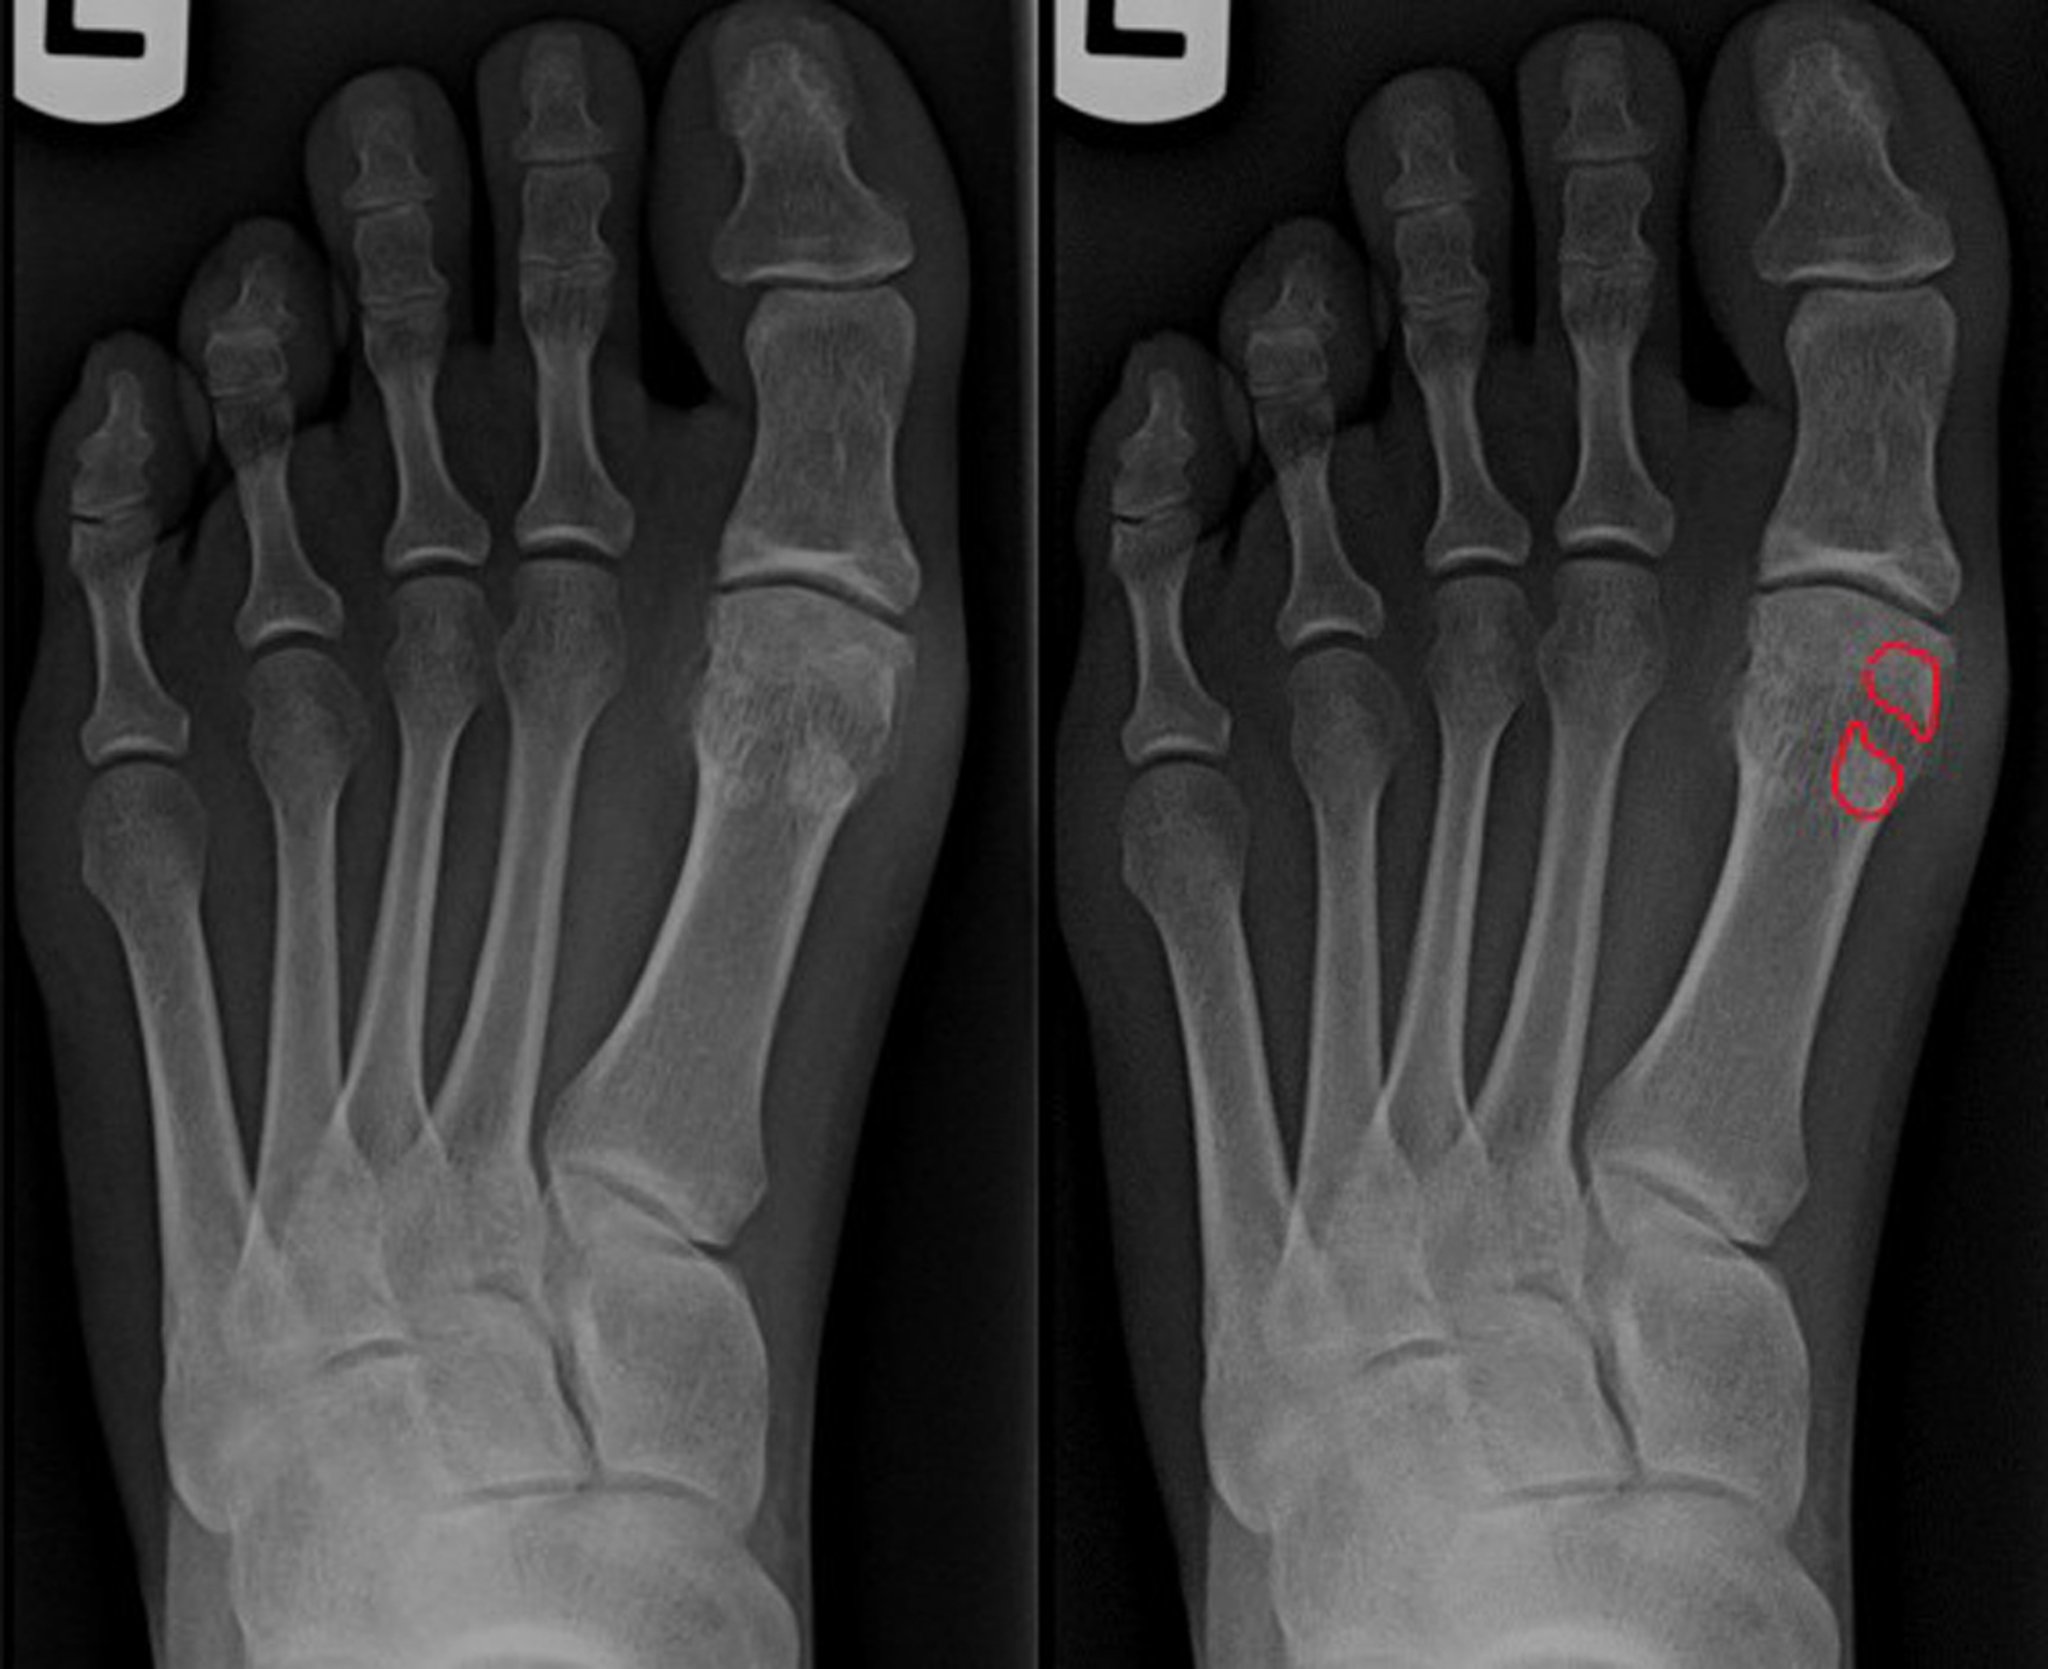

Рентгенограмма при переломе сесамовидной кости

Переднезадняя проекция левой стопы показывает перелом сесамовидной кости. Обратите внимание на увеличенное расхождение отломков кости между фрагментами перелома и неровными линиями перелома на выделенном изображении. Дифференциация двудольной сесамовидной кости важна для обеспечения надлежащей медицинской помощи.

Image courtesy of James C. Connors, DPM.